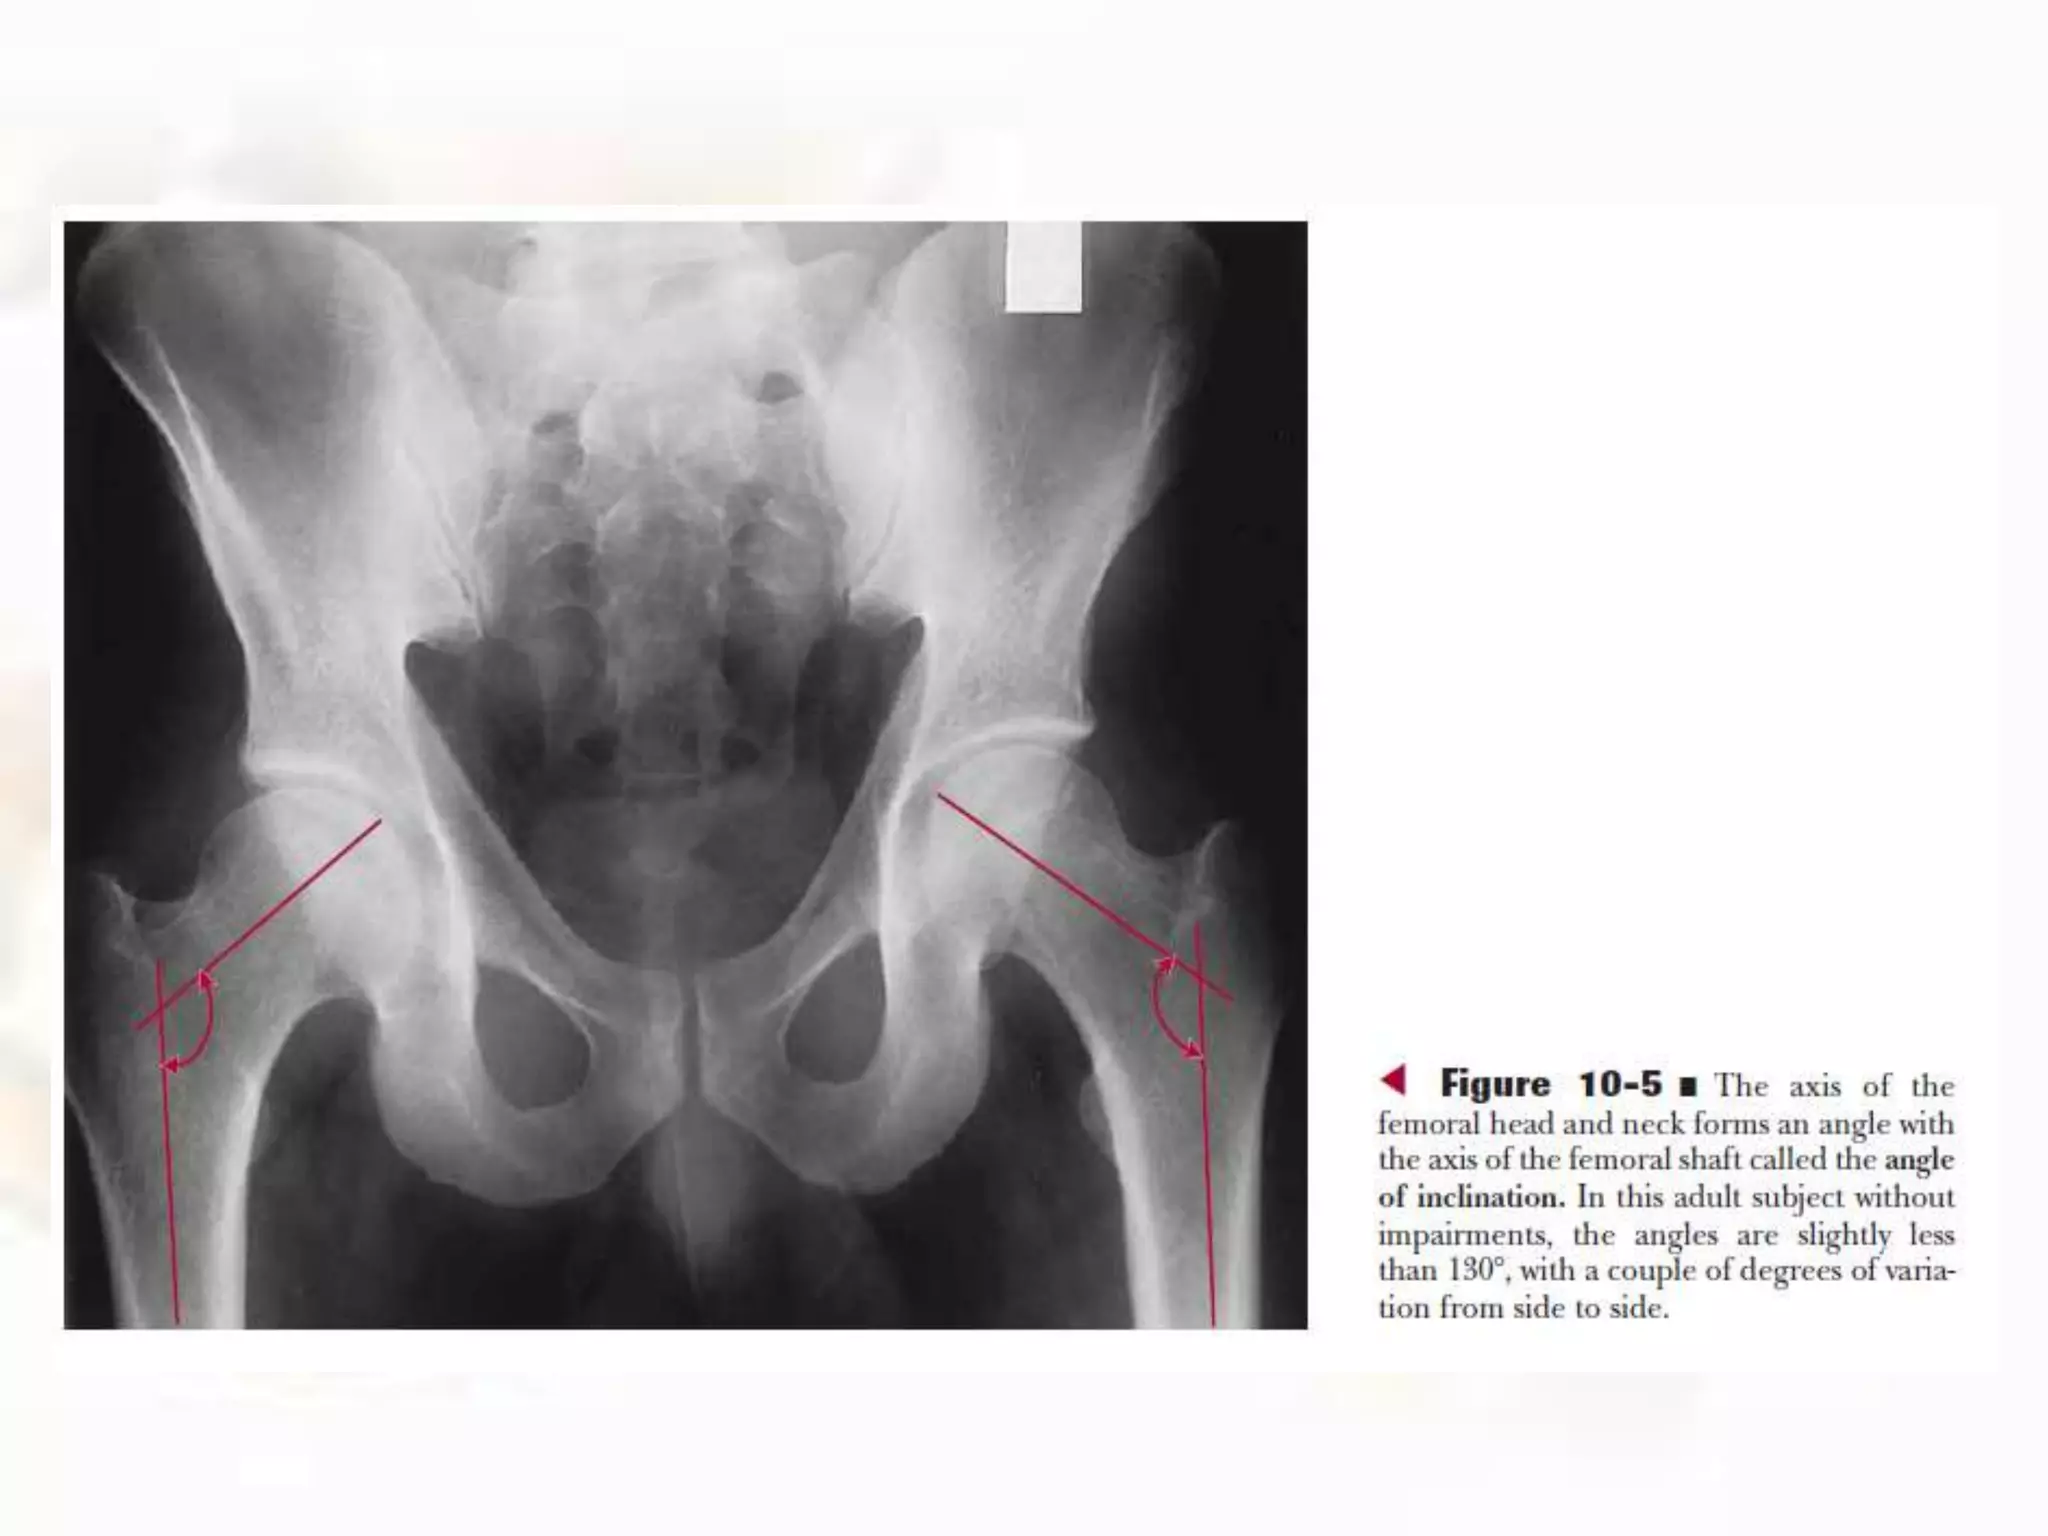

• One angulation (angle of inclination) occurs in the frontal

plane between an axis through the femoral head and

neck and the longitudinal axis of the femoral shaft.

Angle of Inclination of the Femur:

• The angle of inclination of the femur averages 126

degrees (referencing the medial angle formed by the

axes of the head/neck and the shaft), ranging from 115

to 140 degrees in the unimpaired adult.